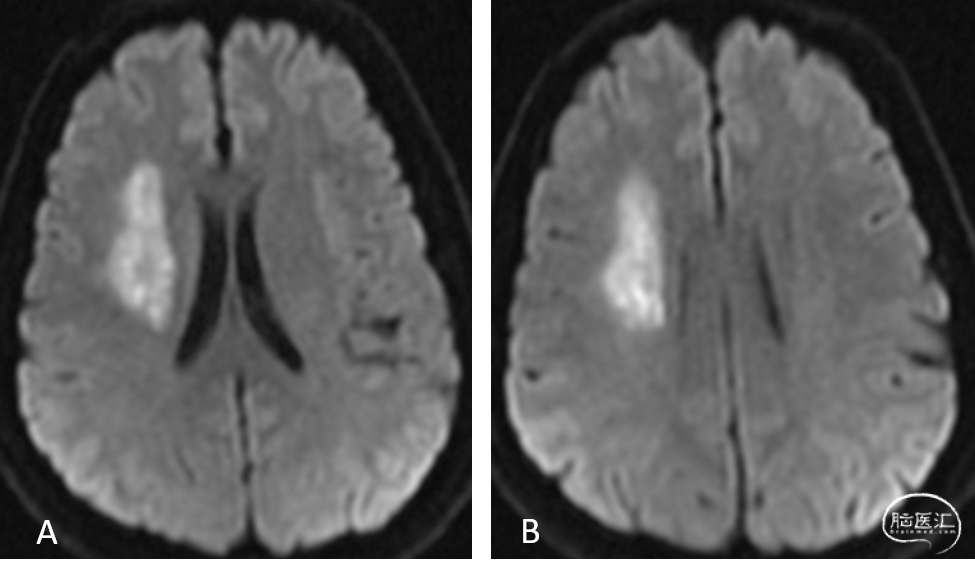

MR提示:右侧半卵圆区新发脑梗死(A、B)。